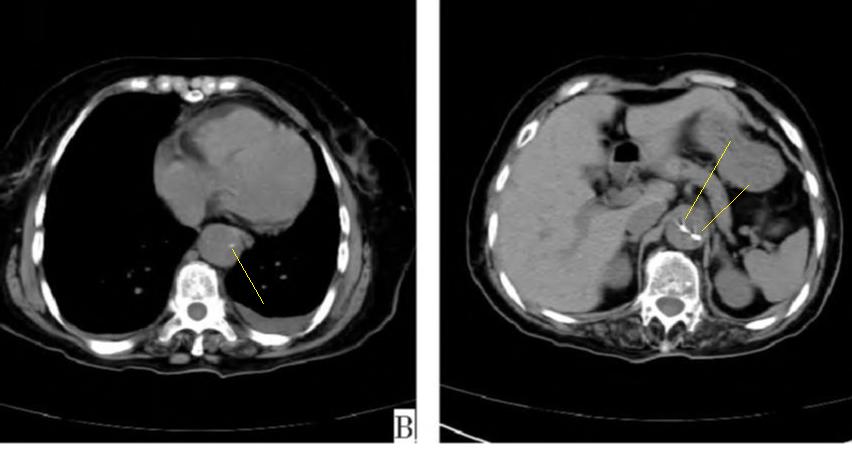

有些小伙伴开始焦急了: 鲁迅你别说了,我们家的CT分辨率低,平扫绝对看不出动脉夹层!

下图的胸部CT平扫,有什么致命的问题?

图15

血管壁钙化啊,老年人很常见啊,能说明个锤子!

注意,看下面,钙化在血管的里面,不是在管壁!难道是血液钙化了?血液钙化?什么鬼?

图16

这不是血液钙化,这是主动脉夹层导致的血管钙化内移!血液不会钙化,因为动脉夹层,导致钙化的内膜被压迫进入血管!

增强CT一看,就一清二楚了!

图17